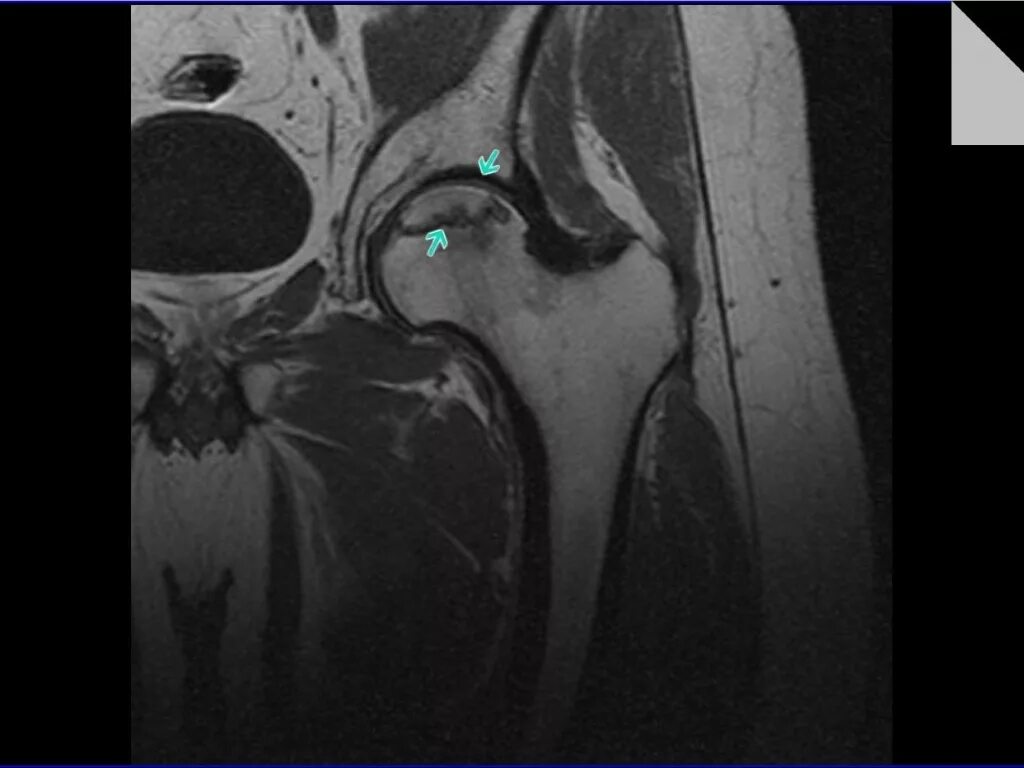

Аваскулярный некроз тазобедренного сустава